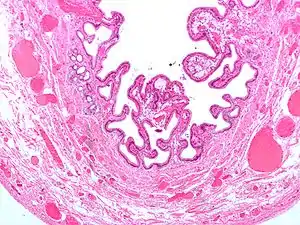

![]() Мікрофотографія жовчного міхура при холециститі Мікрофотографія жовчного міхура при холециститі | |